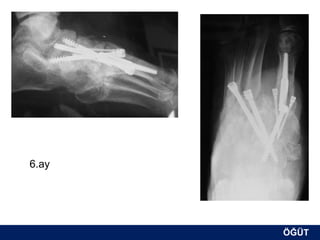

OLGU No 3

FK, 58y, ♂

6.ay

ÖĞÜT

8.ay